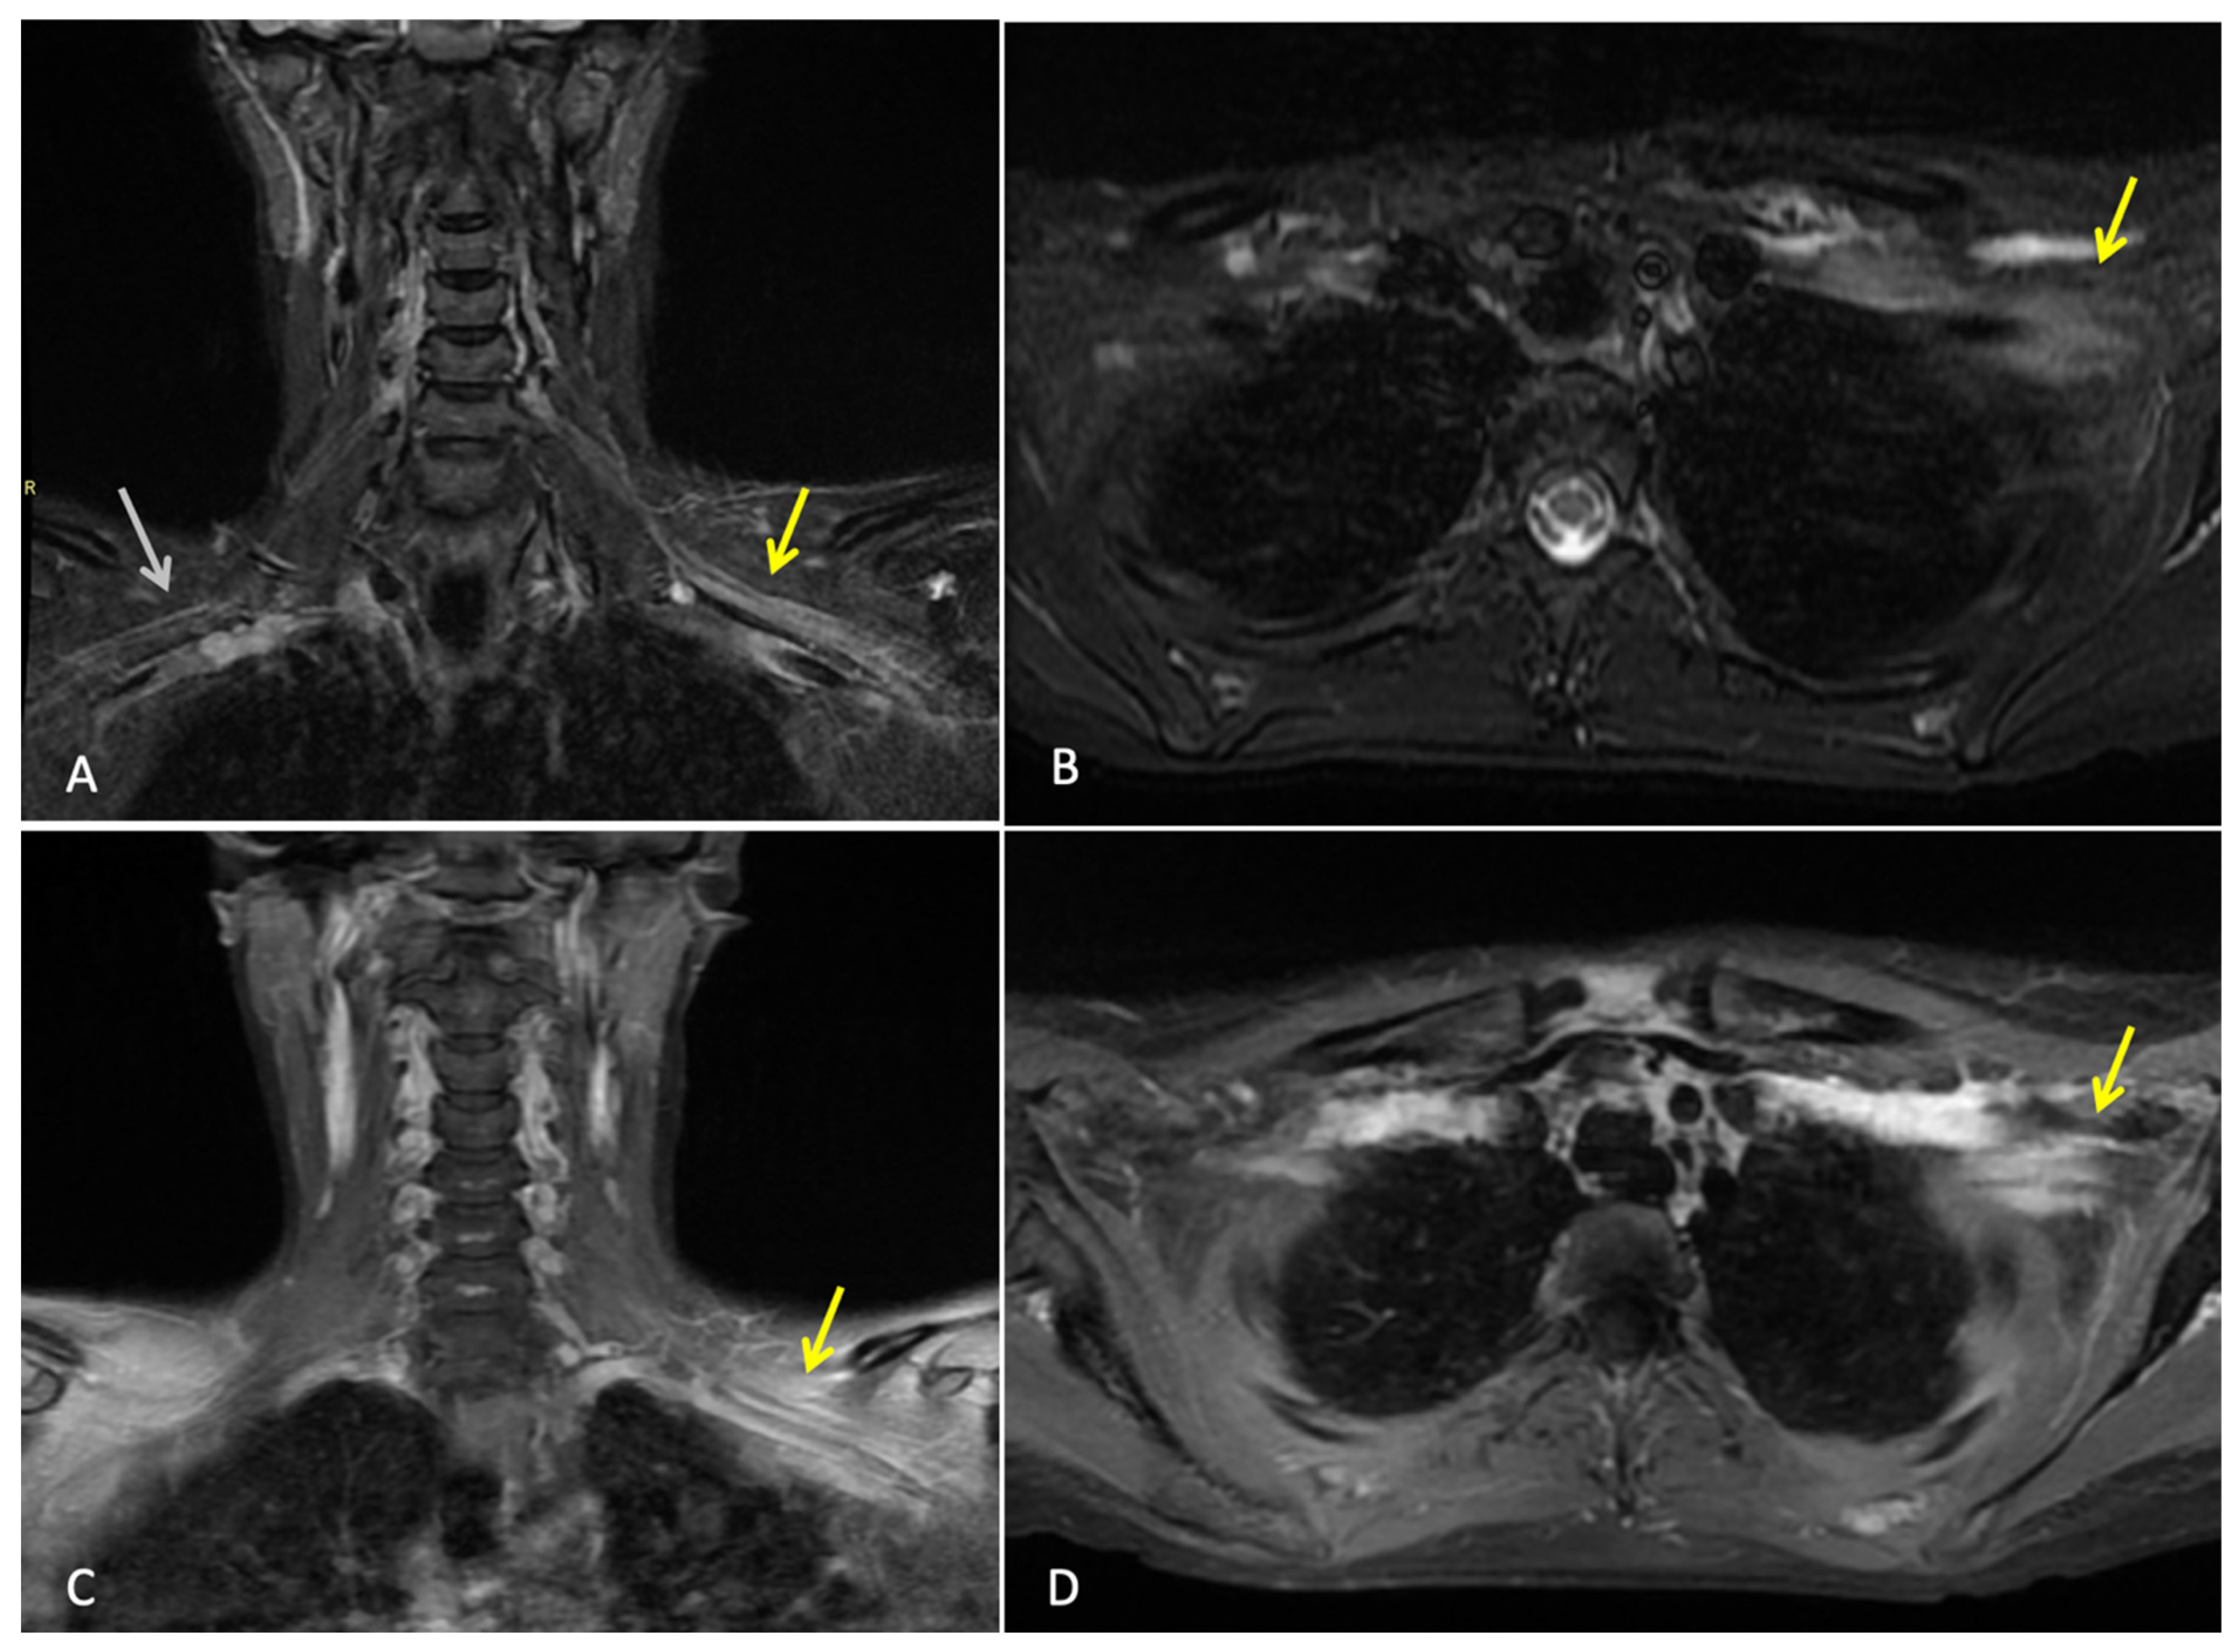

Three months after completing radiotherapy, she developed progressive numbness, paraesthesia, and weakness of the left hand. Examination revealed wasting of the thenar and hypothenar eminences, reduced grip strength, and patchy sensory loss in a C8/T1 distribution. Due to residual cancer burden after surgery, a local recurrence was initially suspected. MRI of the cervical spine and brachial plexus (Figure 1) did not demonstrate metastatic disease, but findings were consistent with brachial plexitis. No recurrent disease was identified on PET-CT, but asymmetric low-grade uptake in the left brachial plexus was also consistent with brachial plexitis (Figure 2), confirming the absence of malignancy. Electromyography (EMG) (Table 1 and Table 2) and nerve conduction studies demonstrated denervation consistent with a lower-trunk brachial plexopathy; onconeuronal antibody serologies were negative.

Figure 1.

MRI brachial plexus: This is a figure. Images (A,B) are coronal and axial T2 STIR images that demonstrate thickening and increased T2 signal of the brachial plexus on the left (yellow arrows). Normal size and signal of the brachial plexus on the right for comparison (white arrow). Images (C,D) are coronal and axial T1 fat-saturated post-contrast images, which demonstrate abnormal hyperenhancement of the thickened brachial plexus on the left side (yellow arrows). Findings are consistent with left brachial plexitis.

In this patient, the presentation of progressing ipsilateral upper limb neurological symptoms (numbness, paraesthesia, and hand weakness) suggested locoregional recurrence, especially given her incomplete pathological response. These symptoms usually point towards locoregional recurrence, radiation-induced brachial plexopathy (RIBP), or metastatic disease. It further required ample imaging and neurophysiological evaluation [18,19,20]. MRI and PET-CT, however, demonstrated no evidence of tumour recurrence, nodal disease, or infiltrative pathology. MRI is integral in differentiating tumour infiltration, radiation-induced fibrosis, and inflammatory plexopathies. The absence of mass effect or structural abnormality in this case reduced the possibility of a malignant or compressive cause. However, electromyography revealed findings consistent with lower trunk brachial plexopathy [18,21].

Furthermore, electrophysiologic features did not suggest the chronic demyelination typical of radiation-induced neuropathy [20]. While genetic radiosensitivity (e.g., ATM mutations) has been implicated in rare cases of severe RIBP, germline testing was negative in this patient [23]. Radiation-induced brachial plexopathy was considered less likely given the short interval from completion of radiotherapy, the subacute and progressive onset of symptoms. Similar characteristic MRI findings of nerve thickening were seen; however, no fibrosis was seen on imaging, which would be characteristic of radiation-induced plexopathy. Electrophysiological features were inconsistent with chronic radiation injury. Taken together, the clinical timeline, mixed imaging findings, and neurophysiologic results adequately support immune-mediated brachial plexopathy as the most plausible diagnosis, favouring an immune-mediated etiology.